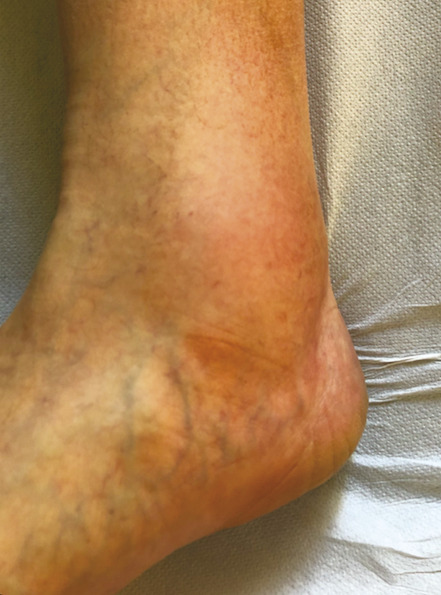

L’œdème veineux est classifié C3. Il est classiquement situé au niveau de la cheville, voire au tiers inférieur de la jambe (fig. 4 ). Il s’agit d’un œdème qui se majore au fil de la journée (œdème vespéral) et qui est favorisé par la station debout prolongée et par la chaleur. Il témoigne du retentissement tissulaire de l’hyperpression veineuse secondaire à la maladie variqueuse.